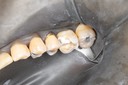

Wayne Chin #12 pre-op